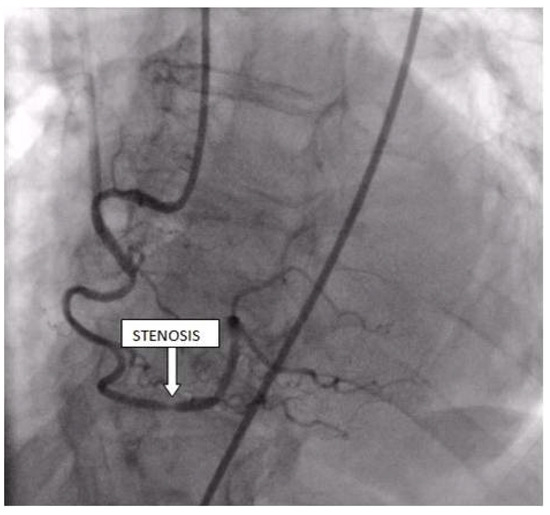

Coronary angiography was performed, showing the left coronary artery (LCA) was without significant lesions (Figure 6). On the right coronary artery (RCA), a subocclusive lesion was registered in the distal segment (Figure 7). Initially, it was thought to be a spasm, but the lesion persisted even after administering nitroglycerin intracoronary. Therefore, a primary percutaneous coronary intervention (pPCI) was performed with the implantation of a drug-eluting stent 16 × 25 mm (Boston Scientific, Marlborough, MA, USA) in the RCA, achieving the optimal result of the intervention (Figure 8).

Figure 7.

Coronary angiography registered a subocclusive lesion in the distal segment of the right coronary artery.